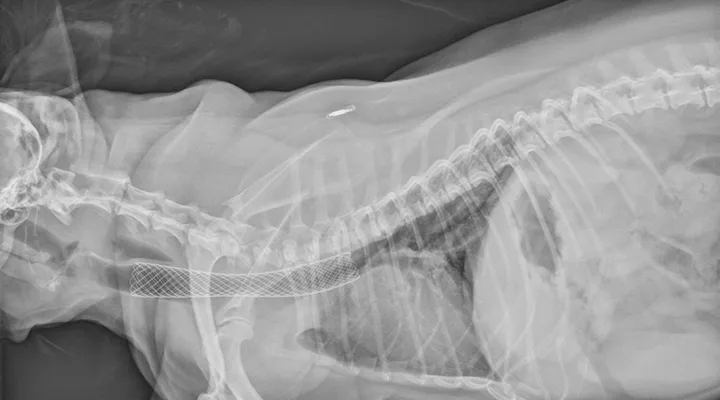

Patients that are severely affected, are refractory to medical management alone, or have life-threatening airway obstruction often benefit from placement of a self-expanding intraluminal tracheal stent (Figure 2). Most patients improve substantially, and survival rates are high; however, most patients require continued medical management.

FIGURE 2 Radiograph of a patient with tracheal collapse treated with a fully deployed intraluminal tracheal stent